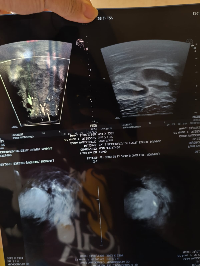

Eu sou a Yasmin e criei essa vakinha para ajudar no tratamento da minha irmã sara q descobriu o câncer de mama recentemente e precisamos de ajuda para pagar o tratamento dela q ficou em torno de 500mil começamos o tratamento mais precisamos de ajuda para continuar o tratamento quem puder nos ajudar agradeço de coração 🙏🏾